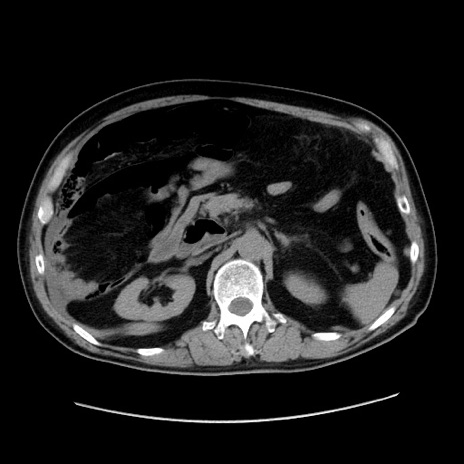

症例30(横断像)

【症例】80歳代男性

【主訴】臍周囲痛

【現病歴】約6時間前から臍下部痛が出現。次第に腹部膨隆・背部痛も生じてきたため来院。背部痛の場所は変化しない。

【身体所見】意識清明、BT 36.3℃、BP  131/87mmHg、P 87bpm、SpO2 100%(RA)、臍周囲自発痛・圧痛あり、反跳痛なし、自発痛部位に一致して板状硬あり、腹部膨隆、腸雑音減弱、CVA tenderness両側陰性。

【データ】WBC 19600、CRP 0.33